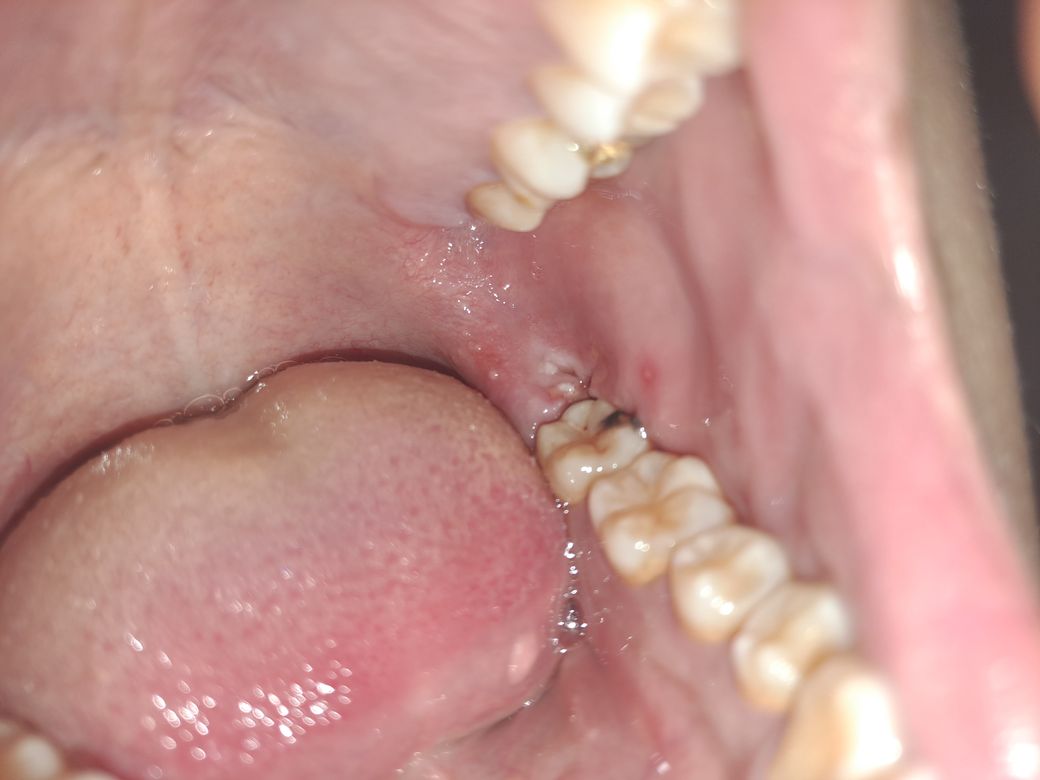

사랑니 발치3일차 드라이 소켓인가요?

사랑니 발치 3일차(이전주 토요일 발치, 질문글 게시는 화요일) 입니다.

과출혈이 있었나 어제즈음 발치부 뿐만 아니라 그 주변에 혈전같은것들이 입 안에 가득해서 가글로 없앴읍니다.

사진 찍은 시점에서 붓기는 전날보다 개선이 되었고,

입에서 이상한 맛이 난다거나 하지는 않습니다마는 뭔가 찌르는듯한 고통이 있어 자다가 깨며, 뭔가 하얀것도 있는지라 비주얼상 의심스러워서 여쭈어 봅니다.

• 1번 째 사진

약간의 염증 반응이 있긴 합니다. 해당 부위 가글로 살살 위생관리 잘해주시기 바랍니다. 통증이 있다면 진통제 복용을 통해 증상 개선해보시기 바랍니다. 특별히 드라이소켓의 양상은 보이지 않습니다.

사진상으로 볼때 드라이소켓으로 보이지는 않으며, 해당부위가 잘 아물고 있는 것으로 보입니다. 염증이 덧나지 않도록 흡연 및 음주는 피하고, 소독용 헥사메딘 가글액으로 가글하여 관리하여 주길 권합니다.

사진에는 문제는 없어보입니다. 통증이 어느정도 있는 것은 정상적이며 심한 통증은 치과 가보시는 게 좋습니다.

사랑니를 발치하고 통증이 심하지 않거나 특별한 냄새가 나지 않는다면 드라이소켓이 아닐 가능성이 높습니다. 사랑니를 발치한 부위가 아무는 데는 이 주 정도가 걸리기 때문에 그 기간 동안 해당 부위를 자극하지 않는 것이 좋습니다.

사진상으로 보면 드라이 소켓은 아닌거 같습니다. 큰 문제가 잇는건 아니니 너무 걱정하지 않으셔도 될것같습니다.